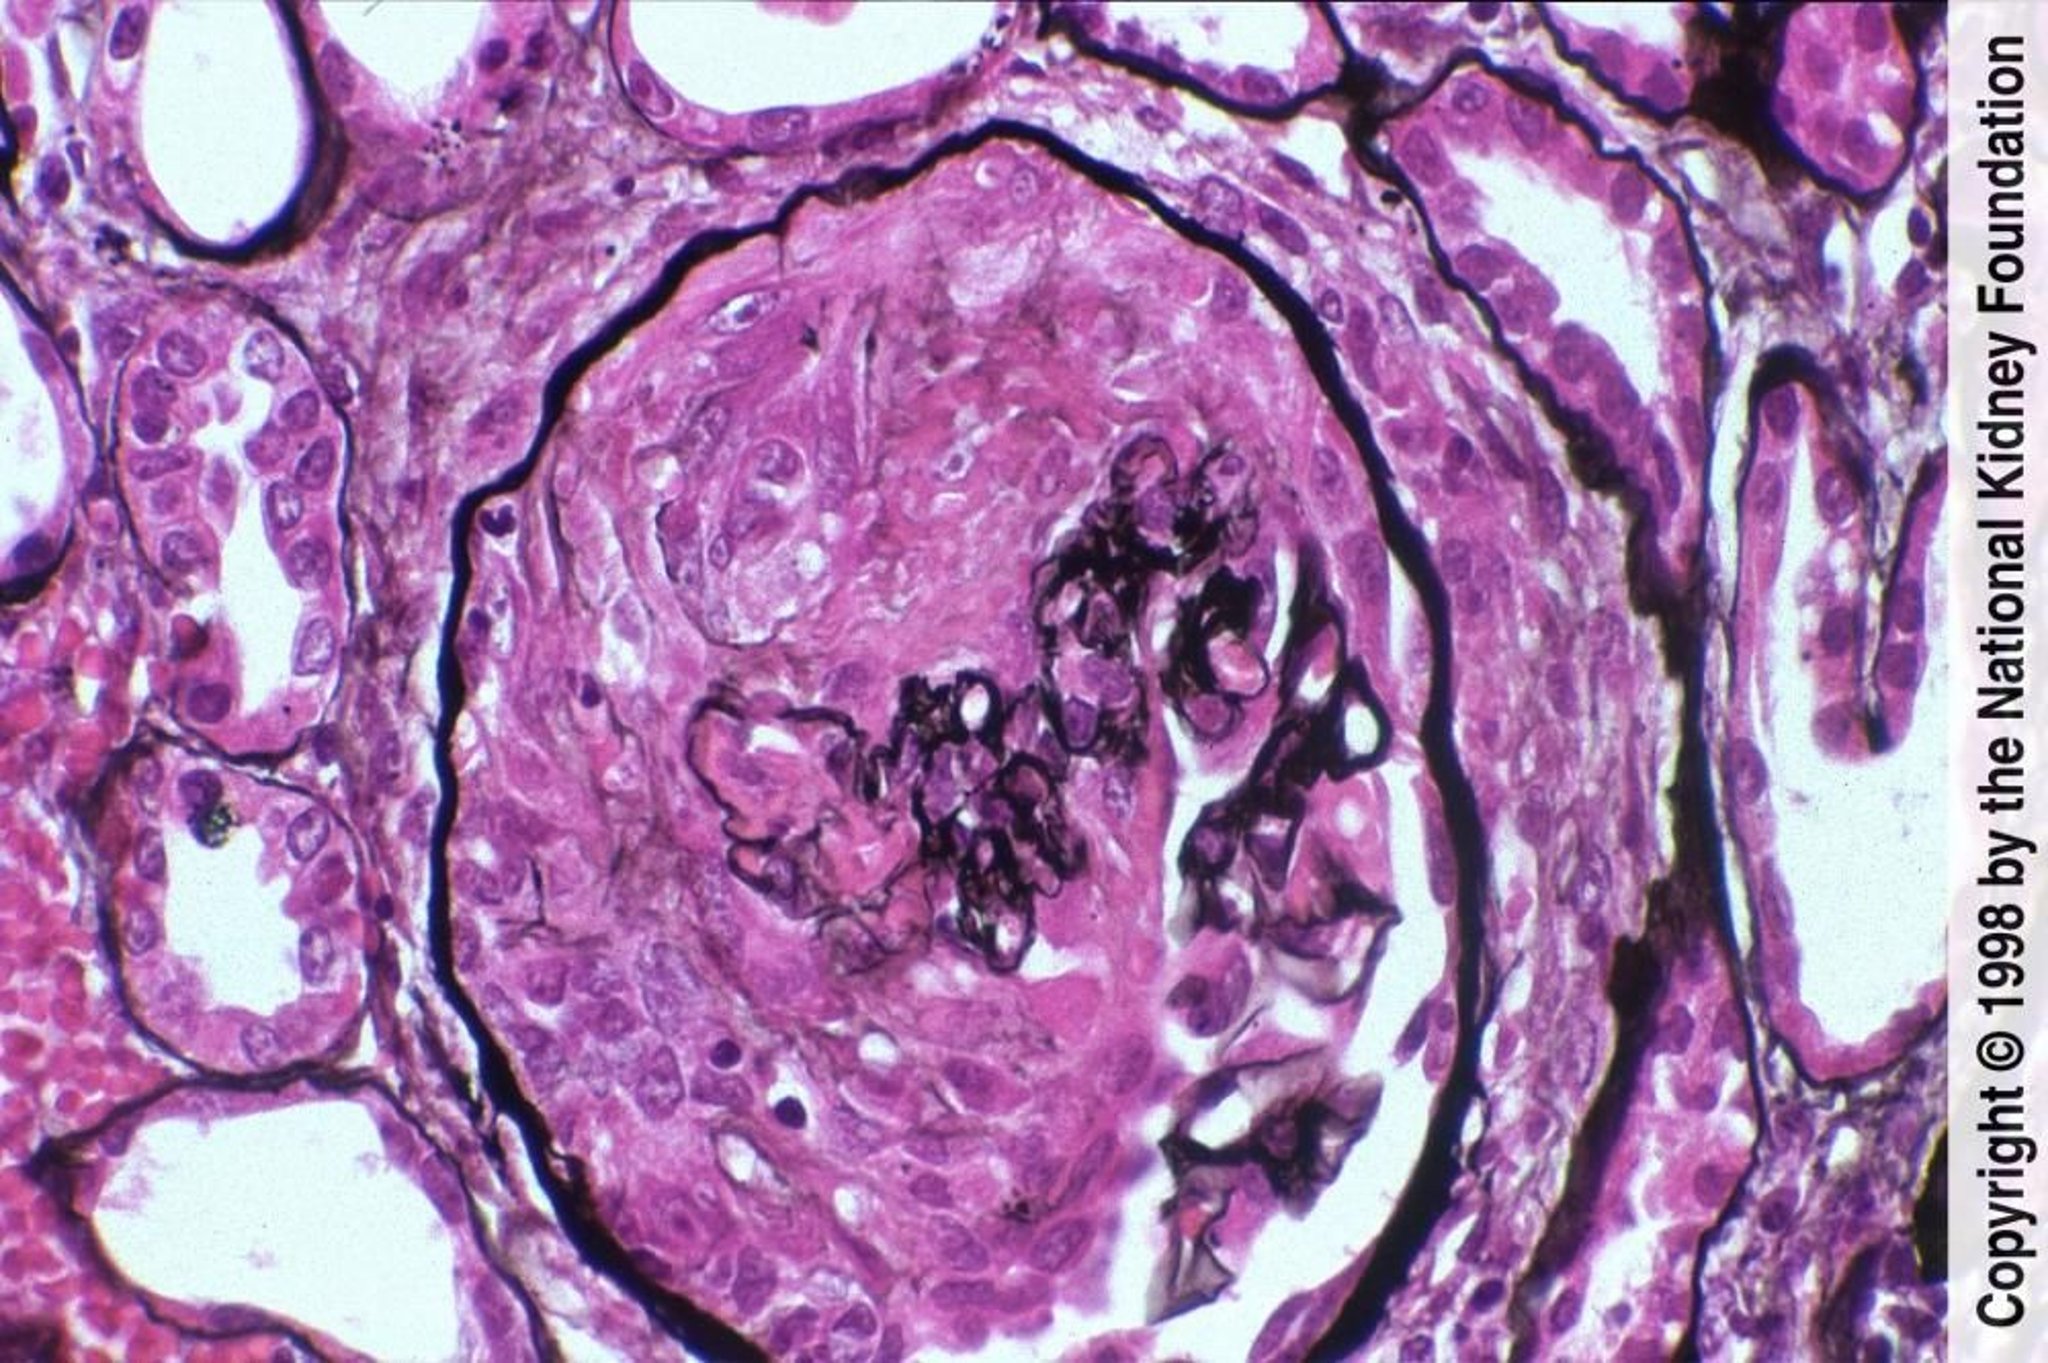

Al microscopio ottico, la malattia è caratterizzata dalla presenza delle semilune, che si formano in seguito alla proliferazione dell'epitelio parietale del glomerulo e alla flogosi concomitante, che porta a un infiltrato di cellule infiammatorie (soprattutto monociti e macrofagi) nello spazio di Bowman. In alcuni casi è possibile osservare proliferazione dell'endotelio o del mesangio.

Con il tempo le cellule che formano le semilune tendono ad essere sostituite da tessuto fibroso.

In assenza di terapia, il decorso clinico è caratterizzato da un rapido peggioramento dell'insufficienza renale. Alcuni reperti istologici, come la presenza di semilune a circonferenza, la fibrosi dei glomeruli e gli infiltrati tubulo-interstiziali sono associati ad una prognosi peggiore, così come la persistenza dell'oligo-anuria. Alcuni autori, comunque, descrivono un miglioramento della prognosi della malattia rispetto al passato, dovuto soprattutto alla tempestività della terapia. La maggiore mortalità si riscontra nella forma pauciimmune (gruppo III): alcuni autori riportano una mortalità del 33% a 4 anni dall'esordio.